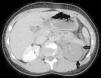

Niño de 13 años sin antecedentes médicos de interés, que acude al servicio de urgencia por traumatismo craneal y abdominal tras caída accidental de bicicleta. Se realiza TAC de cráneo en el que no se evidencian lesiones secundarias al traumatismo. En la TAC abdomino-pélvica se observan 2 focos contusivos en bazo, sin sangrado activo y ausencia de captación del medio de contraste del riñón izquierdo por stop brusco en región proximal de la arteria renal izquierda (fig. 1). Se realizan imágenes de tomografía en fases tardías, observando eliminación normal del medio de contraste por parte del riñón derecho y ausencia de captación de contraste por el riñón izquierdo (fig. 2). Se realiza el diagnóstico de disección de arteria renal izquierda con trombosis completa de la misma, y ausencia de paso de contraste arterial a riñón izquierdo, no siendo posible revascularización renal ni colocación de stent arterial.